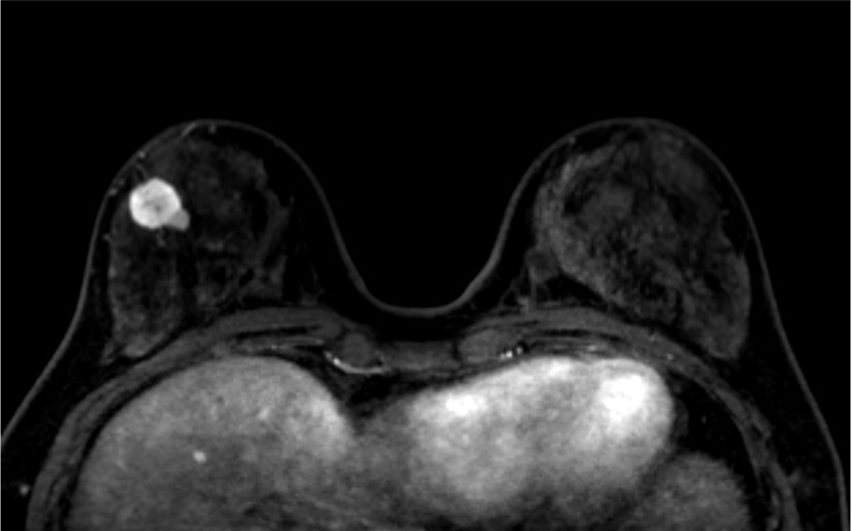

5. Ultrafast DCE

乳癌の病変は、超早期(10相目: 造影剤注入32.5秒後)から急速に造影されている。背景乳腺は超早期では、ほとんど造影されていないが、17相目では軽度増強されている。